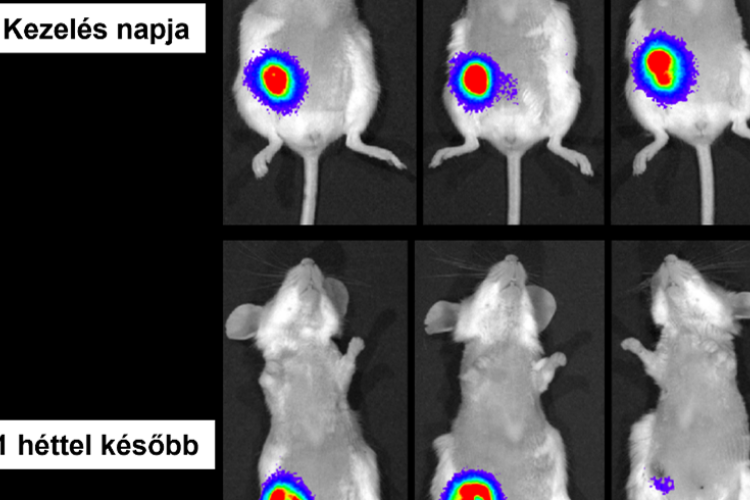

HUN-REN: új lendületet adhat a rák elleni harcnak a magyar kutatók fejlesztése